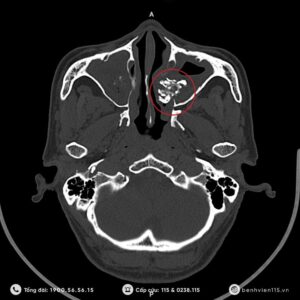

Nếu bạn thường xuyên gặp những vấn đề về sức khỏe: Đau đầu kéo dài...

Viêm xoang kéo dài do nấm: Nguyên nhân khó phát hiện và hướng xử trí...